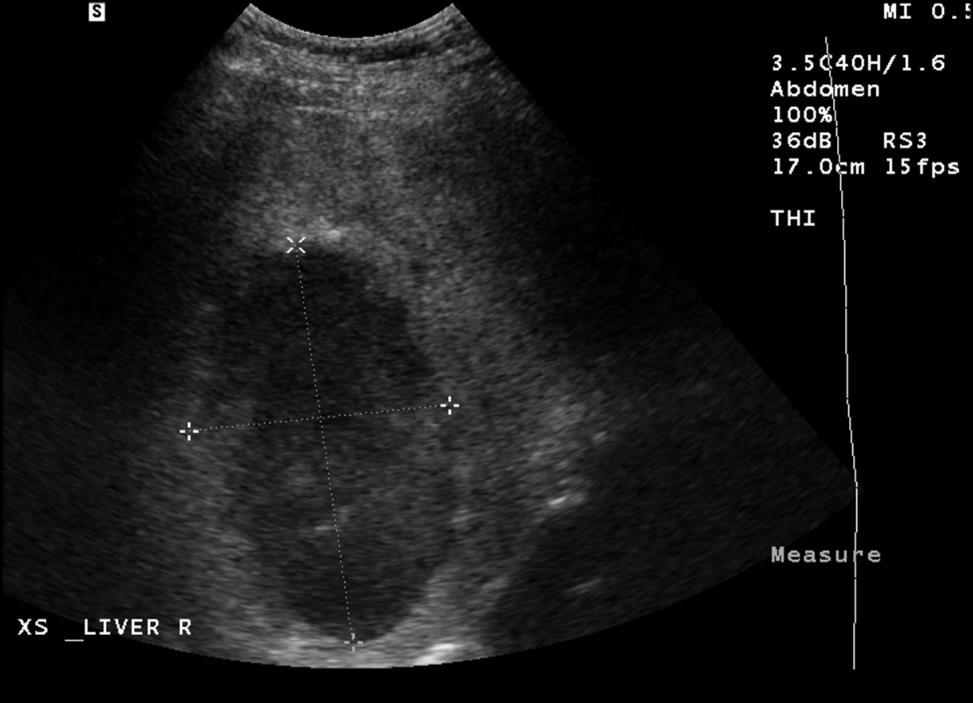

In the ED he was well appearing, but slightly febrile with moderate RUQ tenderness. His laboratory testing was notable for slight liver function test abnormalities and RUQ ultrasound showed a 10 by 6 cm abscess.

Ultrasound appearance did not support Hepatic tumor or Echinococcal Cyst.